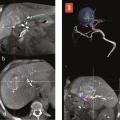

La radiologie interventionnelle a commencé à se développer grâce au progrès de la navigation intra- artérielle à l’aide de cathéters de plus en plus miniaturisés.3 Le positionnement de l’extrémité du cathéter dans l’artère hépatique, voire dans une de ses branches segmentaires à partir d’une voie d’abord périphérique le plus souvent fémorale, permet une obstruction (embolisation)4 [fig. 1 à 4 ], une libération locale intra-artérielle de chimiothérapie5 et plus récemment de microsphères chargées de médicaments6 ou de particules radioactives permettant une irradiation interne sélective du foie.7, 8 Le but est d’obtenir une concentration élevée des agents cytotoxiques au plus près des tumeurs dans le foie avec un faible relargage dans la circulation générale. Enfin, il est possible de placer par radiologie interventionnelle un cathéther dans l’artère hépatique relié à une cham-bre implantable (fig. 5 ). La chimiothérapie est ainsi injectée directement dans le système artériel du foie de façon répétée (en général toutes les deux semaines) avec des concen- trations intrahépatiques de médi- caments bien supérieures à celles obtenues après une injection par voie veineuse. L’objectif est d’obtenir une réduction tumorale qui permette au patient d’être éligible à une éventuelle chirurgie curative.9

Méthodes locorégionales par cathétérisme artériel

Il s’agit de l’injection locale dans le foie de médicaments, d’agent d’embolisation ou d’agents radioactifs. Après cathétérisme artériel à partir le plus souvent de l’artère fémorale et repérage des lésions, le radiologue interventionnel injecte localement différents types d’agents selon le type de métastases, l’extension de la maladie et les traitements antérieurs, après décision en réunion de concertation multidisciplinaire (fig. 1 à 4 ).